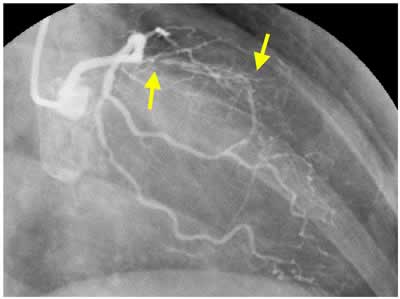

I-3 : months follow-up angio